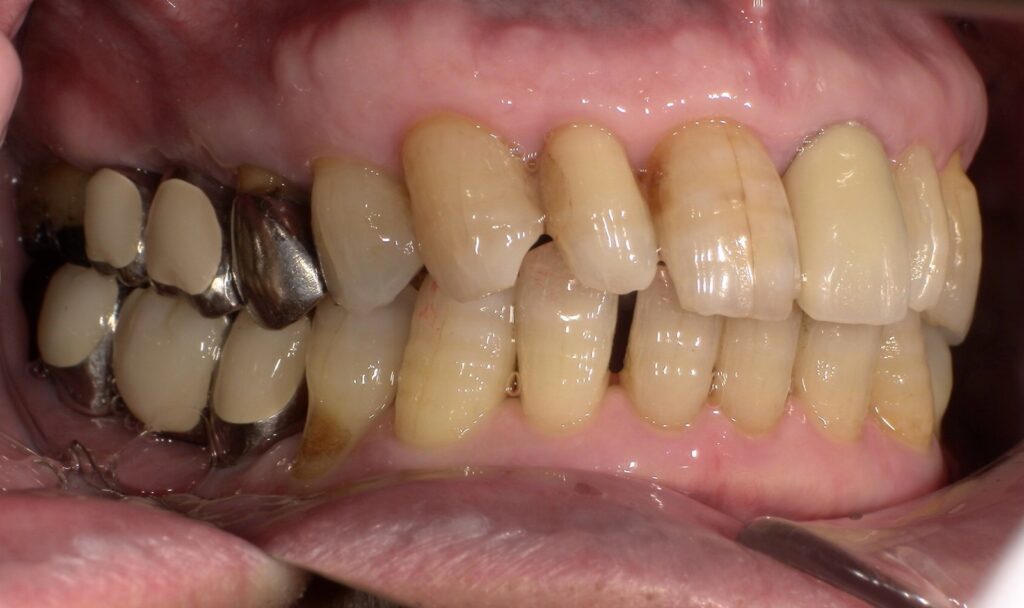

上部構造セット後の側面からの写真です。

患者様より、よく噛めると喜んでいただけました。期間

6か月